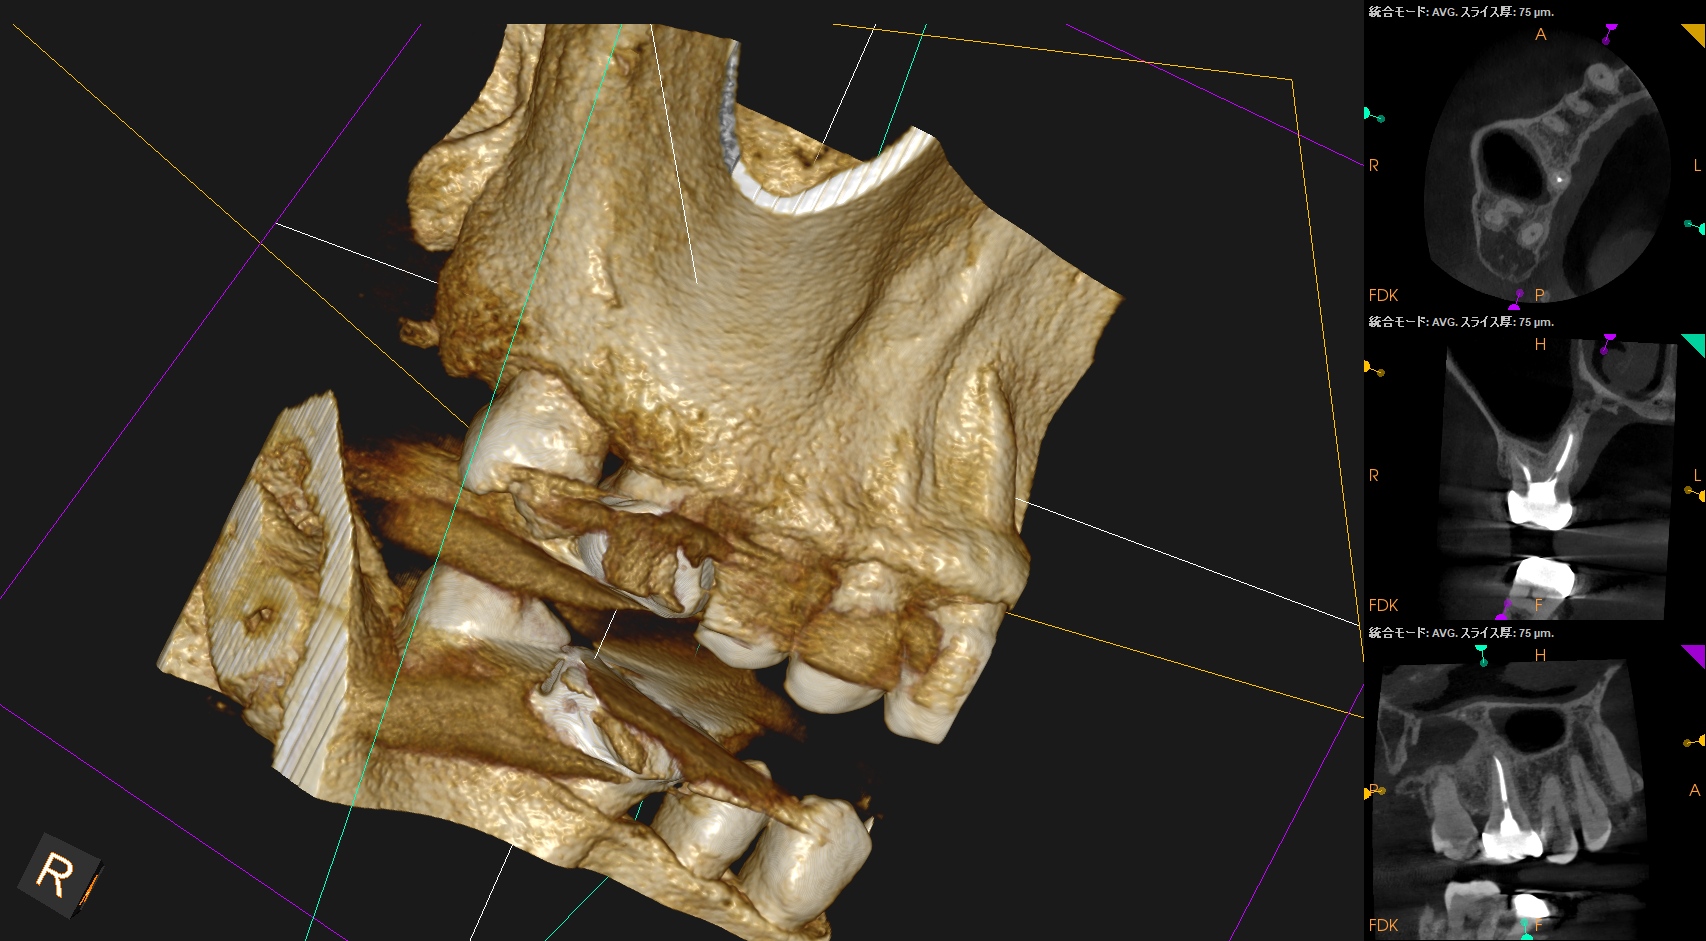

はみ出たBC sealerが消失して歯槽骨と置き換わっている

という臨床的事実だ。

文献にもそうあるが、

BC sealerは組織液と反応して生体親和性の高いハイドロキシアパタイトを生成すると信じられており、それは自家骨に置き換わると信じらている。

炎症性滲出液や嚢胞の存在によってはみ出たシーラーは吸収されると信じられているようだ。

このケースではみ出たBC sealerが歯槽骨に置き換わったのか?私にはわからない。

が、根尖病変が治癒し歯槽骨に置き換わったのは紛れもない事実だ。